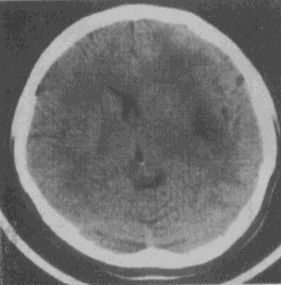

女性,48岁。渐进性右侧肢体活动不灵2个月,无发热。既往无任何病史。CT检查见图,应首先考虑以下哪种疾病。 YZ332_1_39_4.gif

• A.脑梗死

• B.病毒性脑炎

• C.星形细胞瘤

• D.胆脂瘤

• E.AVM